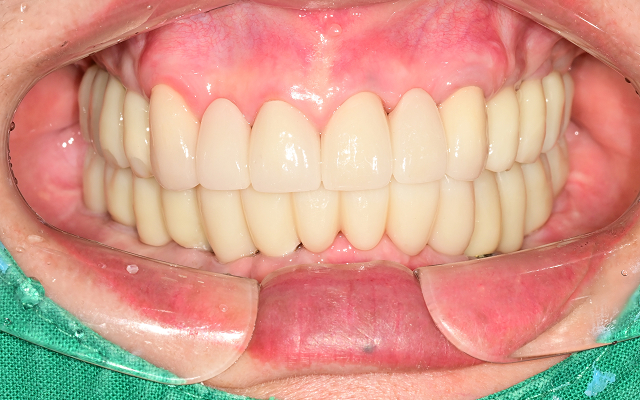

전악 케이스

- 상·하악 전체 보철 설계를 통해 정확한 교합(물림) 회복

- 심미·발음·저작 기능을 종합 고려한 자연스러운 전악 임플란트